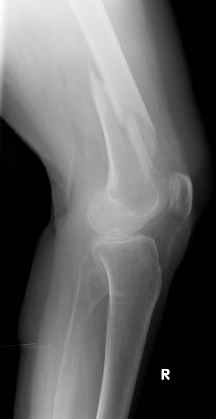

Видно спиральный перелом дистального метадиафиза бедра. У нас бы сделали антеградный закрытый интрамедуллярный остеосинтез.